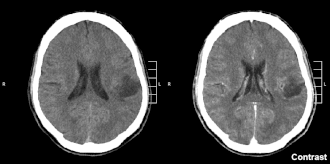

![]() Компьютерная томограмма больного с глиомой левой теменной доли, II степень злокачественности по классификации ВОЗ | |